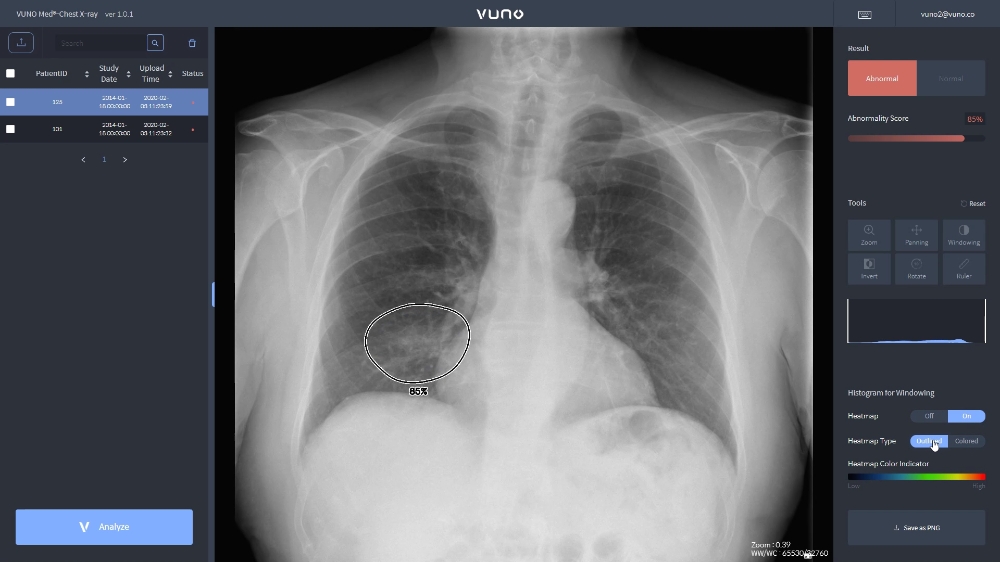

이미지 확대보기뷰노메드 체스트 엑스레이는 폐렴 진단에 도움을 주는 주요 흉부 엑스레이 소견인 '경화(consolidation)'와 '간질성음영(interstitia lopacity)' '흉막삼출(pleural effusion)' 등 총 5개의 소견을 검출하는 기능을 갖춘 흉부 엑스레이 AI 솔류션으로 식품의약품안전처 허가를 받은 제품이다.